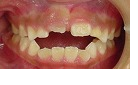

今回は、 子供の 開咬<オープンバイト> です。

症例は小学3年生です。

治療前

治療後

治療前の写真では、このまま大人になってしまうと、ほぼ確実に骨を切る<外科矯正>の適応となってしまいます。 子供のうちに咬合バランスを改善しておきたいものですが、開咬は歯並びが問題ではなく、顎骨の変形が主な原因なので治療が困難です。 しかし、当矯正歯科医院は、開咬は得意分野です。 私の独自の方法で顎骨の形を改善していく事が出来ます。 治療の方向性として、開咬はもちろん、トータルに咬み合わせのバランスを改善します。 治療期間は1年6カ月です。 開咬は複数のタイプがあり、治療方法もそれぞれ異なる為、診査・診断後、お子様に合った治療法をご説明していきます。 もう少し詳しく他の事も知りたい方はHPのトップページをご覧ください。 特にブログの中には最新の情報があります。 当院では、矯正の無料相談を行っております(^^)